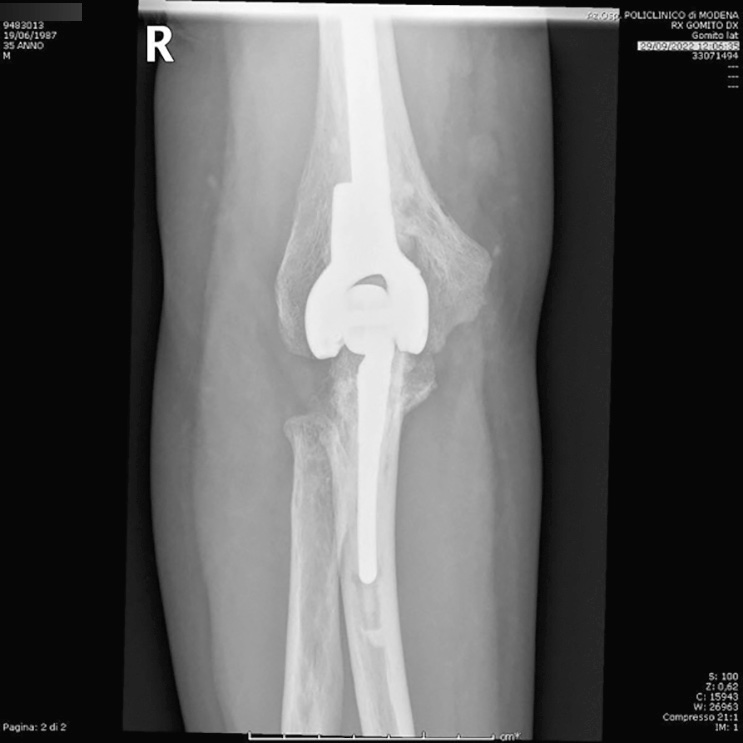

Le protesi totali di gomito si distinguono in: protesi non vincolate, protesi a cerniera vincolate, protesi a cerniera semi-vincolate, protesi di rivestimento (resurfacing) e impianti convertibili. Con questo tipo di impianti è possibile sostituire l’intera articolazione ma anche protesizzare solamente l’omero (emiartroprotesi omerale), il singolo compartimento laterale o il capitello radiale (protesi monocompartimentale e protesi di capitello radiale). Nel 1972, Dee descrisse per la prima volta gli esiti della sostituzione protesica di gomito utilizzando un impianto a cerniera vincolato nei pazienti affetti da AR. I modelli di protesi non vincolata sono in genere caratterizzati da impianti a due componenti con accoppiamento metallo-polietilene. Tra questi, la protesi di Kudo è stata descritta per la prima volta nel 1990 ed è uno dei modelli di protesi di gomito non vincolate più popolari utilizzate per il trattamento dell’AR terminale del gomito. La protesi non vincolata non ha alcuna connessione meccanica tra le componenti omerale e ulnare e tale aspetto determina un discreto vantaggio sulla cinematica del gomito, indicata unicamente nei pazienti con perdita ossea o deformità limitate e con una buona integrità dei legamenti e della capsula articolare, hanno infatti una bassa stabilità intrinseca pertanto fanno affidamento sul bilanciamento dei tessuti molli. L’instabilità postoperatoria è una delle principali complicanze insieme alla mobilizzazione asettica. L’obiettivo delle protesi non vincolate è quello di condividere lo stress da carico dell’interfaccia osso-impianto con i tessuti molli circostanti. Sono descritti in letteratura tassi di sopravvivenza dell’87,8% a 5 anni e del 70,7% a 10 anni. Per quanto riguarda le protesi vincolate, sono raramente utilizzate a causa del loro alto tasso di mobilizzazione asettica e rottura. Tali modelli presentano in genere una cerniera in metallo-metallo e fissazione ossea cementata. La loro indicazione è limitata a casi di salvataggio, come casi di lesioni estese dei legamenti e della capsula articolare o atrofia muscolare o massiva perdita di sostanza ossea. I modelli semi-vincolati presentano protesi a due o tre parti con accoppiamento metallo-polietilene ad alta densità. Tali modelli presentano una lassità intrinseca in varo-valgo che provvede alla dissipazione delle forze. La protesi totale di Coonrad-Morrey è uno dei sistemi semi-vincolati di seconda generazione (Fig. 2) più diffusi che permette un certo grado di movimento in varo-valgo, riducendo la concentrazione dello stress sull’interfaccia osso-cemento (7°-10°di varo-valgo; 7°-10° di rotazione assiale), ottenendo l’effetto di ridurre i tassi di mobilizzazione asettica post-impianto.

Caratteristica di questo impianto è anche l’aggiunta di una flangia anteriore alla componente omerale, la quale consente la protezione dell’interfaccia osso-cemento dallo stress delle forze esercitate nonché la possibilità di inserimento di un innesto osseo anteriore per massimizzare il bone stock nel punto di maggior stress. Risultati soddisfacenti sono stati riportati a nei follow-up a lungo termine. Tuttavia, restano tra le principali cause di fallimento la mobilizzazione asettica e l’usura della boccola. Tra i design di protesi semi-vincolate compare anche il sistema con cuscinetto a cerniera sferica (Discovery Elbow System). Il modello consente una stretta corrispondenza delle superfici articolari, riproducendo l’asse del movimento del gomito. La maggiore area di contatto tra metallo e polietilene riduce il sovraccarico localizzato e le sollecitazioni sul polietilene. Negli ultimi anni, lo sviluppo di impianti convertibili ha dato ai chirurghi la possibilità di modificare una protesi non vincolata in semi-vincolata, creando una cerniera grazie all’applicazione di una componente modulare della protesi ulnare.